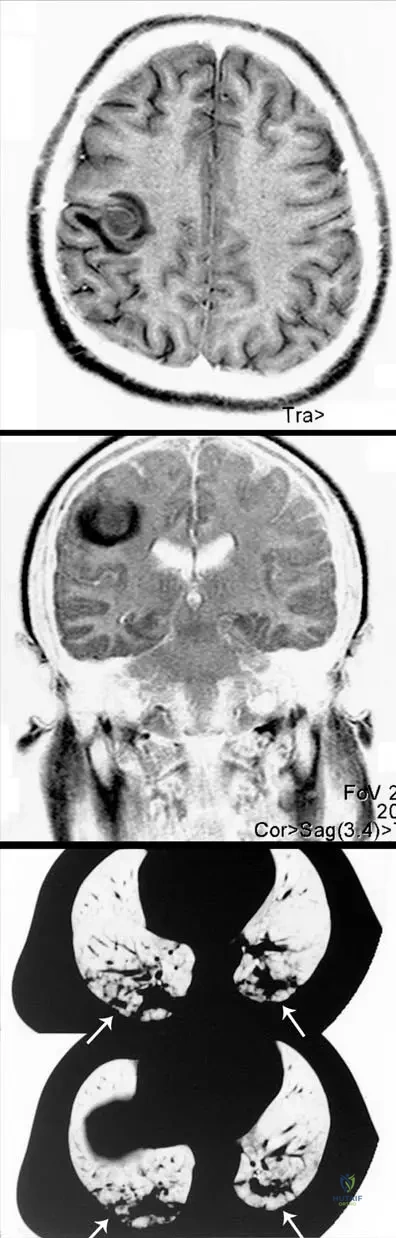

Question 23

View Answer & Explanation

Correct Answer: C

Rationale: The context for Fig. 2.4 describes the MRI findings as "edema and pus formation in the bone marrow and perifocal edema in the surrounding soft tissues," which are hallmark features of acute osteomyelitis on MRI. Main Distractor Rationale: Extensive cortical thickening and sclerosis (A) are more indicative of chronic osteomyelitis, not the acute phase where edema and pus are predominant.

A 12-year-old boy presents with persistent right thigh pain, low-grade fever, and malaise for several weeks. Initial plain radiographs of the femur show a subtle permeative radiographic appearance with an "onion peel" like periosteal reaction. An MRI is subsequently performed.

Rationale: As shown in Fig. 2.4, an MR image of femoral osteomyelitis reveals edema and pus formation in the bone marrow and perifocal edema in the surrounding soft tissues. MRI is highly sensitive for detecting these early inflammatory changes, which are characteristic of osteomyelitis and are often not visible on plain radiographs. Lytic lesions with sclerotic margins (A) are more typical of chronic osteomyelitis or other benign bone lesions, and MRI's primary role here is not just to confirm a lytic lesion. Ruling out a stress fracture (B) might be part of a differential, but MRI's main utility in osteomyelitis is for infection assessment. Assessing joint effusion (D) is a secondary finding. Cortical thickening (E) is a late finding, better seen on CT or plain films, but MRI excels at soft tissue and marrow changes.

Question 26

Rationale: Fig. 2.5 a–c, which describes the same patient with *Lactococcus*-osteomyelitis, shows cranial MRI with metastatic purulent foci in the brain and a chest CT scan with metastatic purulent foci in the lung. These metastatic foci are described as causing a life-threatening condition. Therefore, the new neurological and respiratory symptoms are highly suggestive of systemic spread of the infection. While chronic osteomyelitis (B) can develop, it typically doesn't present with acute, life-threatening systemic symptoms. Antibiotic side effects (A), allergic reactions (D), or superinfection (E) are less likely to explain the specific pattern of brain and lung involvement seen in the images.

Rationale: Fig. 2.5 a–c explicitly shows cranial MRI with metastatic purulent foci in the brain and chest CT scan with metastatic purulent foci in the lung in the same patient with *Lactococcus*-osteomyelitis, causing a life-threatening condition. The neurological symptoms (headache, confusion, seizures) are consistent with brain involvement, and respiratory symptoms (shortness of breath, cough) are consistent with lung involvement. This indicates systemic dissemination of the infection. Adverse reactions to antibiotics (A) or co-infection (D) are less likely to present with such specific multi-organ involvement. A localized abscess (B) would not explain systemic symptoms. Septic arthritis (E) is a localized complication, not a systemic one.

Question 31